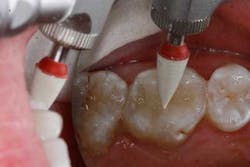

The tooth was prepared and a total etch technique utilizing 37% phosphoric acid was performed (Figs. 3 through 5). After the etchant was rinsed, a desensitizer was placed and blotted to leave a moist dentin surface for bonding (Fig. 6). The bonding agent was applied; the ethanol solvent was air evaporated using a warm air dryer; and the adhesive light-cured for 10 seconds (Figs. 7 and 8).